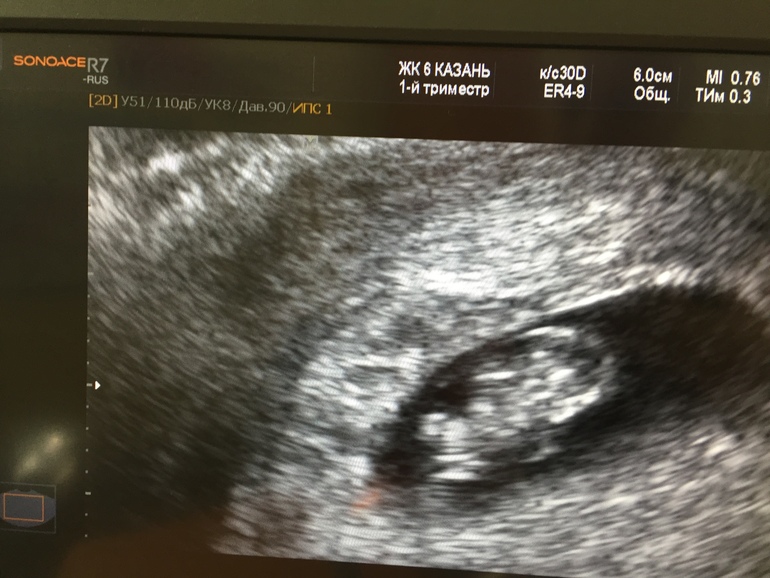

УЗИ 8,5 недель

вот она моя куколка, моя красоточка. КТР соответствует, все хорошо (ттттттт)